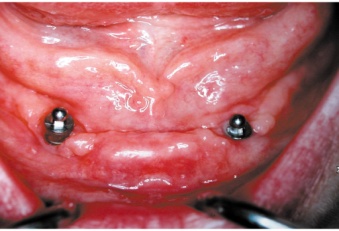

Bezzubá čelist je hlavní indikací pro ošetření pomocí implantátů. Zejména celkové zubní náhrady v dolní čelisti mají velice nízkou stabilitu a držení díky velkému úbytku kosti.

S pomocí zubních implantátů můžeme díky různým kotevním systémům (třmeny, kulové hlavy, Locatory) zajistit stabilitu a držení protézy nebo při použití většího počtu implantátů zhotovit pevné náhrady – můstky nalepené nebo našroubované na pevno na implantáty.

S těmito typy náhrad můžeme dosáhnout perfektní funkci, výbornou estetiku, fonetiku a současně zajistit u pacienta možnost dobré hygienickou péče a čištění, která je pro životnost implantátů velice důležitá.